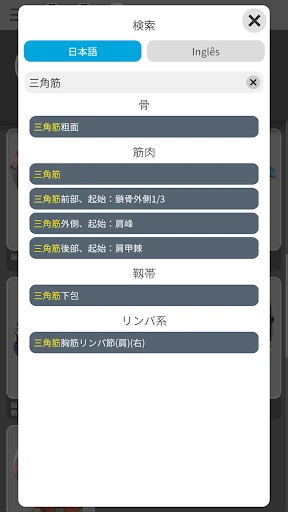

この「解剖学 - 3Dアトラス」、ただのビジュアルツールにとどまりません。かなり多くの情報が詰まっています。例えば、各部位の詳細な説明や、医学用語の解説も充実しているので、学習にはもってこいです。特に、試験勉強中の学生さんには非常に役立つことでしょう。

私のお気に入りの機能の一つは、特定の部位を選択すると、その部位に関する詳細な情報が表示されることです。これにより、単なるビジュアルだけでなく、知識を深めることができるのです。